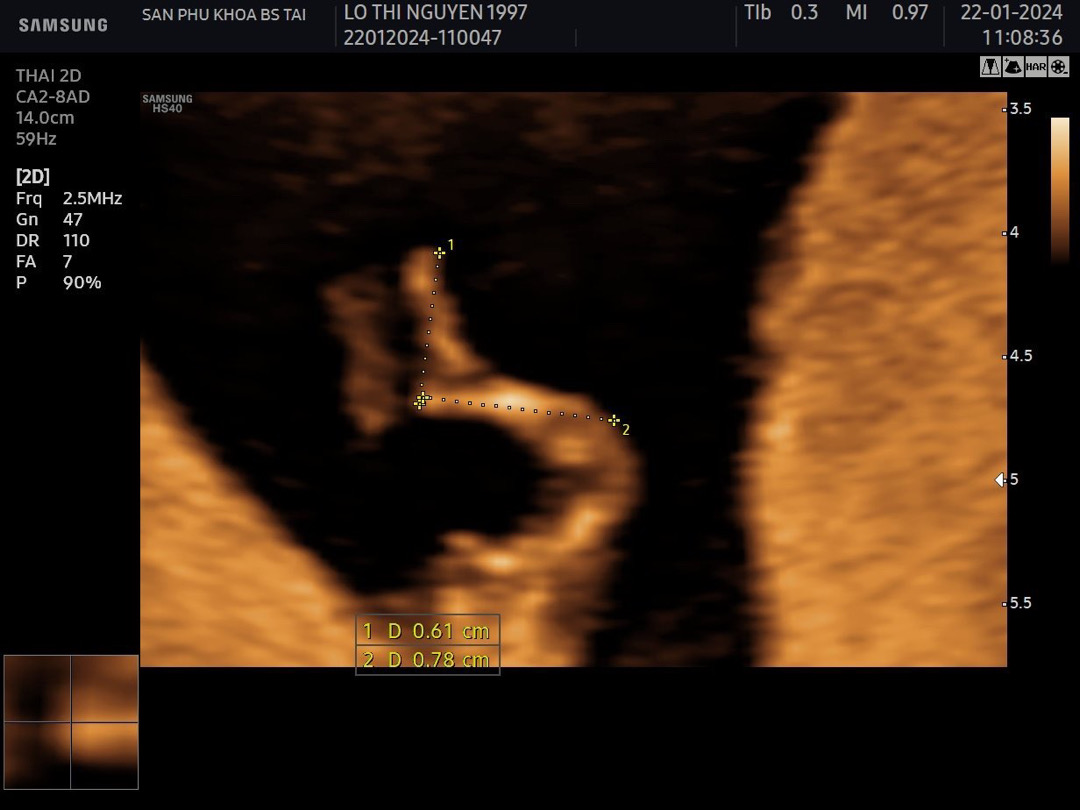

Nay đi siêu âm con mk 11 tuần0 ngày. Ai có kinh nghiệm nhìn giúp mk là trai hay gái k ạ, tại mk tò mò quá 😅

B này zai nhé mom, thấy rõ chim xinh rồi nè, chúc mừng mom nha